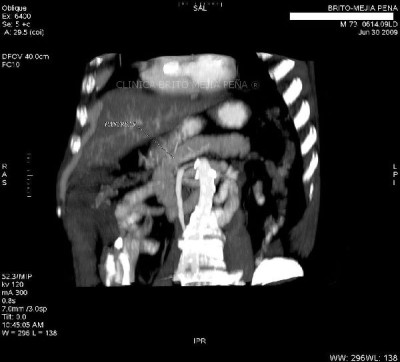

Urotac 3D

Post Image

Urotac fase excretoria